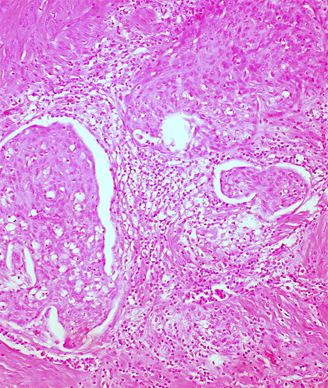

A 71-year-old woman not on hormone replacement therapy presented with uterine bleeding. Dilation and curettage revealed complex hyperplasia with atypia, focal clear-cell features, and endocervicitis. Endometrial intraepithelial carcinoma was suspected.